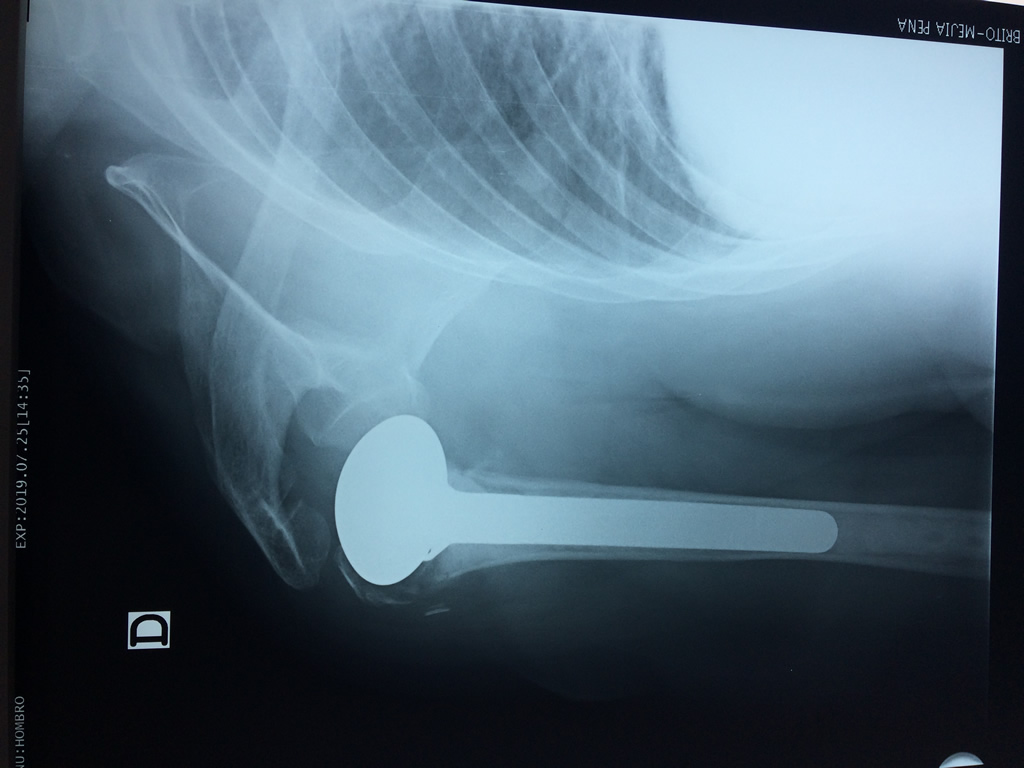

La principal articulación del hombro es la que une la cabeza del húmero con la escápula, recibe el nombre de articulación escapulohumeral y presenta dos superficies articulares, una de ellas corresponde a la cabeza del humero que tiene forma semiesférica y la otra es la cavidad glenoidea de la escápula, estas superficies están recubiertos por cartílago que permiten un movimiento suave e indoloro.

Exteriormente una envoltura de tejido blando circunda el conjunto, es la llamada cápsula articular que está reforzada por varios ligamentos que le dan estabilidad e impiden que los huesos se desplacen más allá de sus límites fisiológicos. Un conjunto de músculos y sus tendones se unen a las superficies de los huesos y hacen posible la movilidad de la articulación, entre ellos es muy importante el manguito rotador formado por cuatro músculos que proporcionan movilidad y estabilidad al hombro.

Varias estructuras transparentes en forma de saco llamadas bolsas serosas, permiten el deslizamiento suave de los diferentes componentes móviles. El hombro es la articulación con mayor amplitud de movimientos del cuerpo humano.